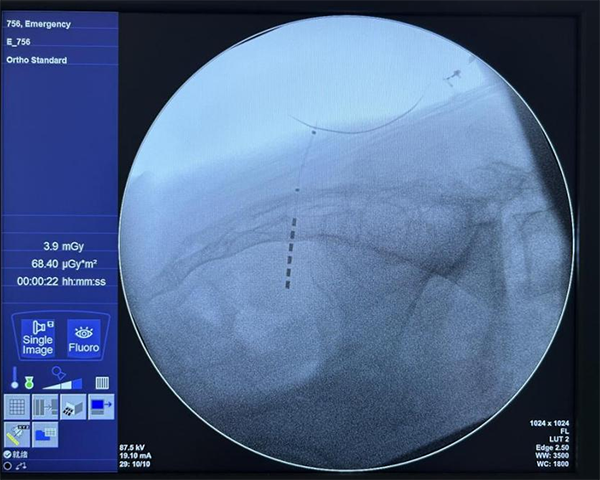

图为新型6触点电极成功植入患者体内